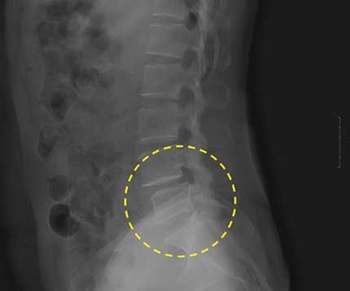

<사진>척추불안정증과 척추전방전위증이 동반된 환자의 X-레이. 원안의 척추 배열이 불안정한 것을 확인할 수 있다. /나누리병원 제공

결국 척추뼈마디 배열이 불안해지면서 신경다발이 지나가는 척추관이 좁아지거나, 척추뼈마디가 밀려나가는 현상도 발생하기 쉬워진다. 즉 척추관협착증, 척추전방전위증 등 또 다른 퇴행성척추질환을 동반하는 것이 척추불안정증의 특징이다.

척추불안정증은 대개 다리쪽 신경을 압박한다. 발병 초기에는 주로 허리와 엉덩이에 통증이 생기고, 오래 서있거나 앉아 있지를 못한다. 허리를 구부리거나 뒤로 젖히는 것도 힘들다. 나이가 들면서 증상이 심해지는 경우가 많다. 증상이 심해지면 통증이 하체로 내려와 다리가 아프거나 저려 제대로 걷지를 못하게 된다. 불과 몇 십 미터만 걸어도 통증이 심해져 쉬어야만 한다. 오래 누워있으면 허리가 아파 밤에 숙면을 취하기도 어렵다.